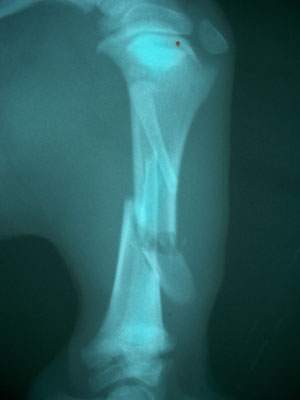

Θηλυκό σκυλάκι ακαθόριστης κυνηγετικής φυλής 2,5 μηνών και 4,5 kg με τμηματικό κάταγμα τουλάχιστον 7 ημερών μεσότητας διάφυσης αριστερής κνήμης και περόνης.

Μετά την ανάταξη του κατάγματος και την συγκράτηση του απολλύματος με μεταλλικό ράμμα τοποθετήθηκε στην έσω επιφάνεια της κνήμης μεταλλική πλάκα 2,7mm και 3 κοχλίες 2,7 mm στο κεντρικό τμήμα και 3 κοχλίες 2,7 mm στο περιφερικό.Κατά την διάρκεια του χειρουργείου διαπιστώθηκε ο,τι κλώτσησαν 4 από τους κοχλίες. 3 περιφερικά και γι΄ αυτό τοποθετήθηκαν δύο μεταλλικά ράμματα και 1 κοχλίας κεντρικά και τοποθετήθηκε 1 μεταλλικό ράμμα.